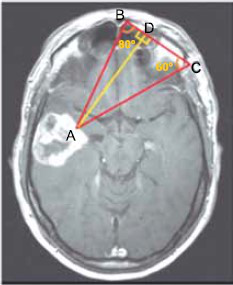

A imagem, obtida por tomografia computadorizada, revela a presença de um tumor cerebral no ponto A. O método de triangulação sobre essa imagem indica que as medidas dos ângulos A!$ \widehat{B} !$C e A!$ \widehat{C} !$B são, respectivamente, 80° e 60°.

Adotando-se tg 60º = m, tg 80º = n e utilizando-se a medida !$ \overline{BC} !$ de igual a !$ \mathcal{l} !$, a distância do ponto A ao segmento de reta !$ \overline{BC} !$ , indicada na figura por !$ \overline{AD} !$ , será igual a